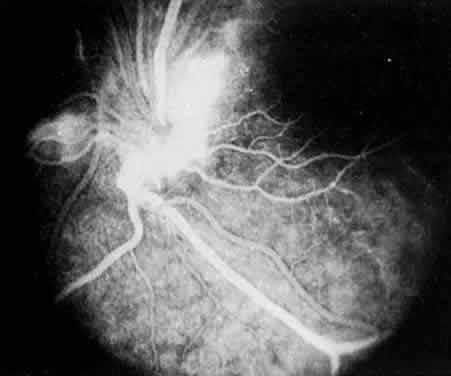

FLUORESCEIN ANGIOGRAPHY AND VITREOUS FLUOROPHOTOMETRY

In pars planitis, fluorescein angiography shows diffuse leakage from the retinal venules and capillaries, without any predilection for the inferior retinal vasculature (Figs. 5 and 6).28 Similarly, vitreous fluorophotometry in patients with pars planitis also shows no predilection for vascular leakage in the inferior peripheral retina.29 These findings suggest that snowbank is most likely a sequela from ocular inflammation, that inferior peripheral retina periphery is not the source of inflammation in pars planitis, and that pars planitis is not a localized inflammatory response of the inferior retina.

Fig. 5. Pars planitis. Fluorescein angiogram showing diffuse venous and capillary leakage.

Fig. 6. Pars planitis. Fluorescein angiogram of pars plana membrane showing diffuse leakage indicating neovascularization.